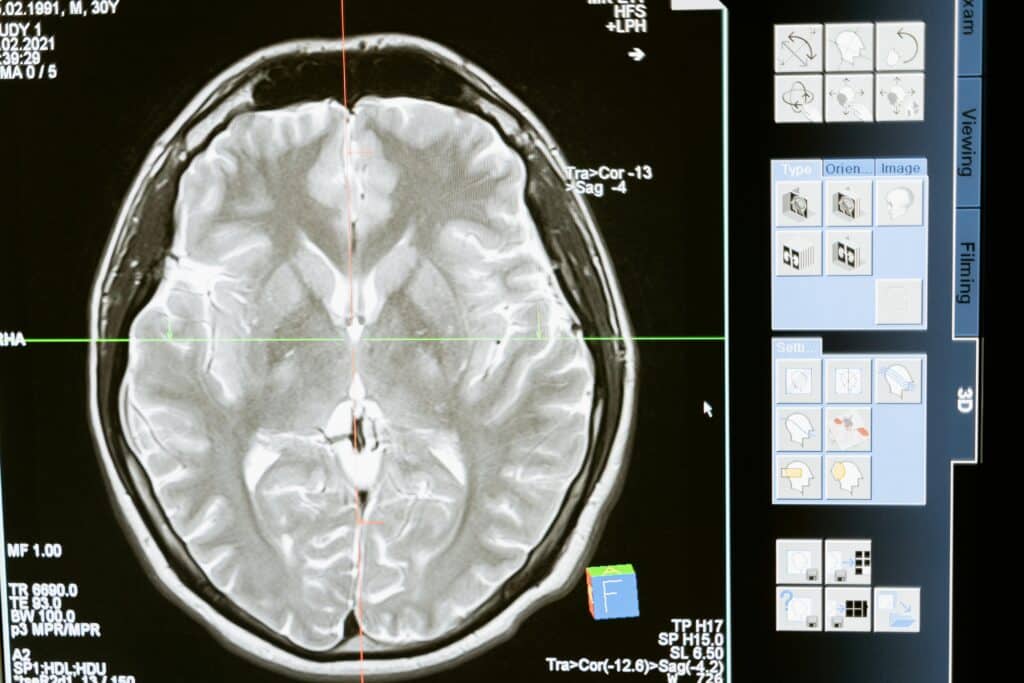

- Imaging Tests: MRI or CT scans can help identify areas of inflammation or brain swelling.